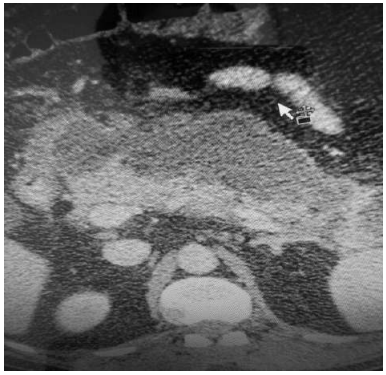

Um paciente de 78 anos de idade queixa-se de dor abdominal aguda em epigástrio e flanco direito há vinte dias. Já procurou dois serviços anteriormente, sendo que, no primeiro, ficou internado por cinco dias e recebeu o diagnóstico de colecistite aguda e, no segundo, foi observado um problema no pâncreas (SIC). Não tem consigo nenhum documento oficial. Chegou ao pronto-socorro com dor em epigástrio (4/10), desidratado, descorado, anictérico e afebril. Apresentava massa palpável em epigástrio,sem sinais de irritação peritoneal. Exames laboratoriais revelaram: hemoglobina de 11 mg/dl; leucócitos de 14.000; glicemia de 108; amilase de 92; e lipase de 72. Realizou, também, a tomografia abdominal com contraste mostrada no corte abaixo.